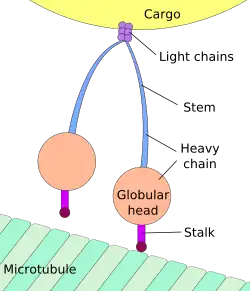

Axonal transport, also called axoplasmic transport, is a cell process not only responsible to the movement of protein and membrane to its axon, but also responsible to the movement of molecules that destined for degradation from the axon back to the cell body. Movement toward the cell body is called retrograde transport; movement toward the synapse is called anterograde transport.

Axonal transport is essential to neuron cell growth and survival. Axon of neuron is 1,000 or 10,000 times the length of the cell body, but contains no ribosomes, which means that it is unable to produce protein. All proteins and membrane must synthesize proteins in neuronal cell body or neuron cell dendrite, and then transport back to the axon. The motor protein kinesin is a motor protein used during anterograde processes while dynein is used in retrograde processes .